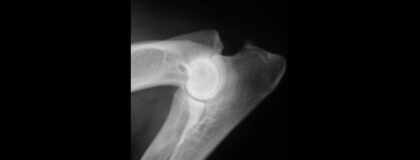

Online-Seminar: Röntgendiagnostik der Hüft- und Ellbogengelenkdysplasie

In diesem vetinar lernen Sie die Grundlagen der Röntgendiagnostik der Hüft- und Ellbogengelenkdysplasie beim Kleintier kennen. Durch Beispiele wird der strukturierte Zugang zur Einstufung der Ellbogengelenkdysplasie gefestigt. Es werden zunächst die Lagerung und Röntgentechnik besprochen. Im Anschluss lernen Sie die Graduierung der Hüftgelenksdysplasie nach FCI im Vergleich zu anderen Graduierungssystemen und die Graduierung der Ellbogendysplasie nach IEWG. Fallbeispiele aus Zuchtuntersuchungen und von klinisch erkrankten Patienten runden die Fortbildung ab.